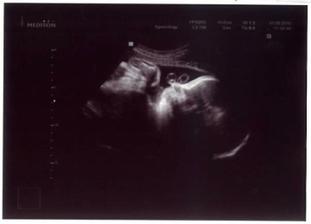

22.12.2009 (10.tt) - Ultrazvuk: viděli jsme naše miminko, slyšeli poprvé bušit srdíčko a máme první fotečku.

02.03.2010 (20.tt) - Genetický ultrazvuk:máme podrobně prozkoumané miminko, vše je v pořádku, pouze zjištěna mírná dilatace ledvinných pánviček cca 5 mm, dostali jsme doporučení na kontrolní ultrazvuk za měsíc.

03.03.2010 (20.tt) - Na vlastní žádost další ultrazvuk u jiného Dr., abychom dostali mimi na videu - máme úžasný zážitek a ještě úžasnější památku na celý život!

30.03.2010 (24.tt) - Kontrolní ultrazvuk: v pořádku, dilatace ledvinných pánviček 4 mm, ale prý netřeba to dál sledovat, tak máme radost.

31.05.2010 (33.tt) - Ultrazvuk + poradna

- UZ: vážíme 2 096 g, máme trochu méně plodové vody, ale to je prý kolísavé - jinak vše v normě, mimi už je hlavičkou dolů.

14.06.2010 (35.tt) Kontrolní ultrazvuk + poradna

- UZ: vážíme cca 2 590 g, máme stále méně plodové vody, ale neva, mimi je hlavičkou dolů; stále trvající oboustranná diletace pánviček ledvinných